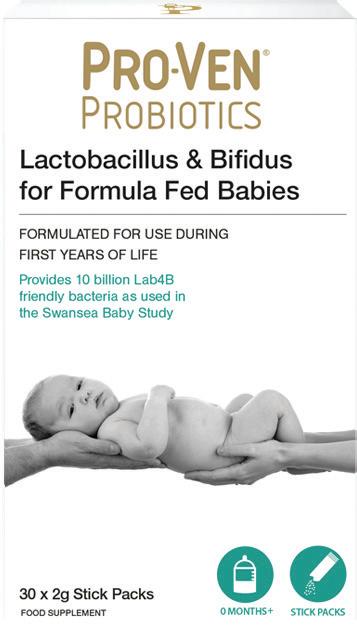

Прашок

Производ